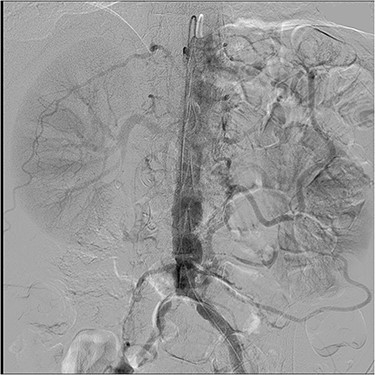

The patient is a 58-year old male who was being evaluated for inguinal hernia repair. His past medical history included CAD with prior stenting of the left circumflex artery, diabetes with a HbA1c of 5.7 and an 80-pack year smoking history. He reported a 37 kg unintentional weight loss over 6 months with postprandial abdominal pain and nausea. In addition, he had exertional angina relieved by rest and sublingual nitrates. He had an abdominal CT scan for evaluation of the hernia, and this demonstrated severe atherosclerotic abdominal aortic disease with occlusion of the origin of the celiac and superior mesenteric arteries and patency of the inferior mesenteric artery. This was confirmed by mesenteric angiography which demonstrated occlusion of the celiac and SMA with a large mesenteric collateral originating from the inferior mesenteric artery (Fig. 2). This artery had a 90% orifice stenosis. With his cardiac history and symptoms, he underwent coronary angiography, which demonstrated significant left main and 3-vessel CAD (Fig. 1A and B). Left ventricular function was preserved with no valvular heart disease by transthoracic echocardiography.

Mesenteric angiogram: both the celiac and superior mesenteric arteries are totally occluded, and the IMA provides the meandering mesenteric collateral. There was a 90% stenosis at the orifice of the IMA.